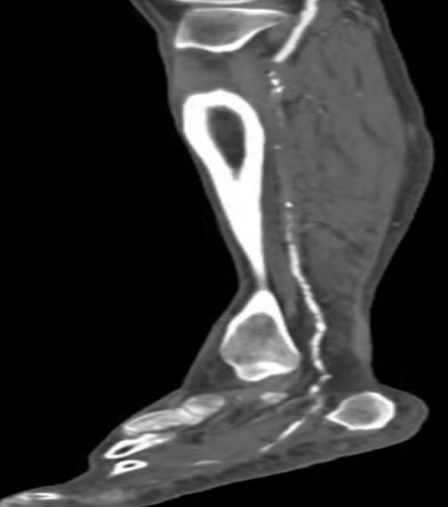

下肢动脉CTA